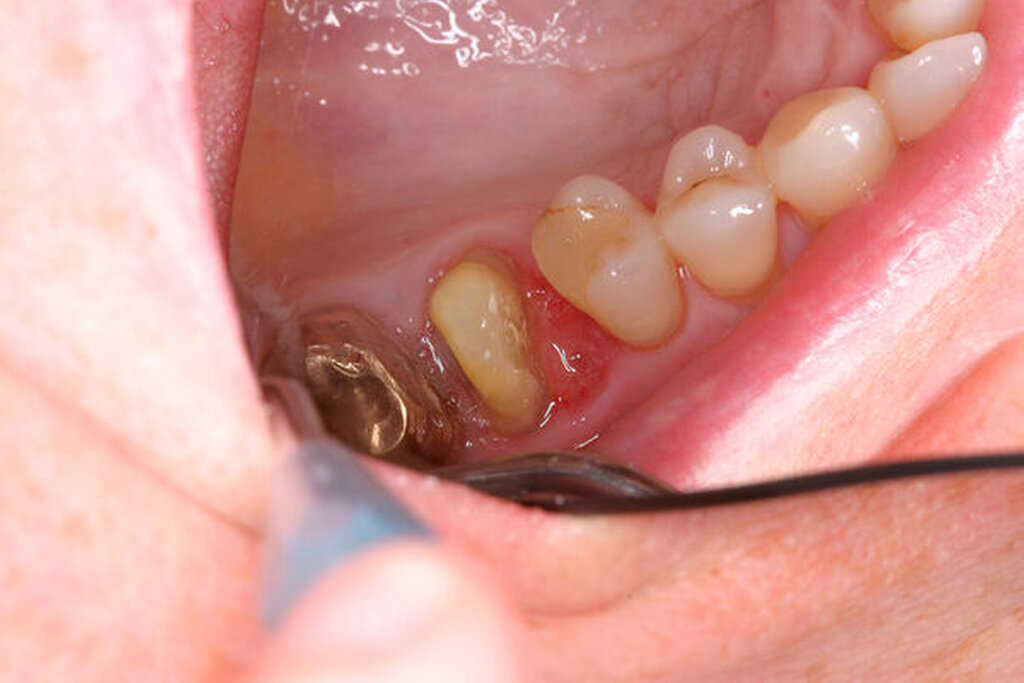

Nach der Anästhesie erfolgt bei einer beabsichtigten Entfernung einer der beiden bukkalen Wurzeln ein Ertasten der vestibulären Furkation. Wir halten es für ratsam, von der Furkation nach okklusal eine deutlich sichtbare Markierung mit einem wasserfesten Stift anzuzeichnen und diese Linie okklusal halbkreisförmig um die zu entfernende Wurzel zu verlängern. Das erleichtert die Orientierung beim Absetzen des zu entfernenden Zahnanteils. (Abbildung 1a).

Eine 46-jährige Patientin klagte 2014 über wiederkehrende Beschwerden an Zahn 16, die sich auch nach einer endodontischen Behandlung nicht besserten. Wiederholt waren submuköse Abszesse aufgetreten. Lokalisiert war die Sondierungstiefe stark erhöht, was auf eine Längsfraktur der mesiobukkalen Wurzel hindeutete. Die Patientin wurde über die Möglichkeiten der Amputation der mesiobukkalen Wurzel sowie alternativ der Extraktion des Zahnes aufgeklärt und entschied sich für den Versuch des Zahnerhalts mittels Teilamputation der mesiobukkalen Wurzel.

Ein 59-jähriger Patient stellte sich erstmals 2015 mit rezidivierenden pochenden Beschwerden und zeitweise zusätzlich auftretendem Pusaustritt an Zahn 16 vor. Klinisch zeigte sich ein ausgeprägter Attachmentverlust distal mit bis apikal sondierbarer distobukkaler Wurzel, Furkationsbeteiligung und Pusaustritt sowohl über den Parodontalspalt als auch durch einen distobukkal gelegenen Fistelausgang. Zunächst erfolgte die endodontische Behandlung des Zahnes 16 mit anschließender systematischer PA-Therapie. Bei persistierender parodontaler Problematik an 16 wurde die Möglichkeit der Teilamputation der distobukkalen Wurzel mit dem Patienten diskutiert, um die Hygienefähigkeit und damit die Prognose des Zahnes zu verbessern. Auch über die Extraktion als Alternative wurde der Patient aufgeklärt. Er war allerdings motiviert, seinen Zahn so lange wie möglich zu erhalten.